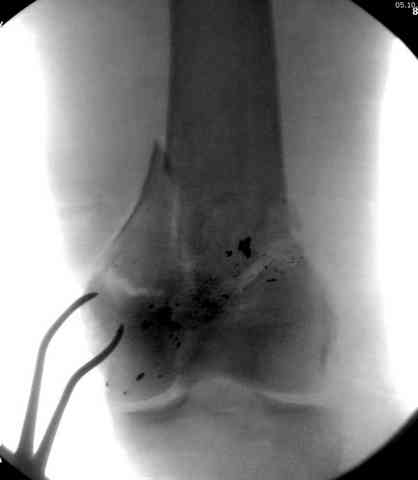

Пуля от ПМ - очевидно, что ранение было т.н. низкоэнегетическим, что подтверждается в том числе спокойным состоянием мягких тканей в этом, уже отсроченном периоде.

Здесь представлены несколько случаев лечения огнестрельного перелома

1 Проксимальный перелом бедра, антеградный гвоздь

2 внутрисуставной перелом дистального бедра с удалением пули

3 сегментарный перелом бедра с переломом Хоффа фрагментом, сделано из минимального доступа